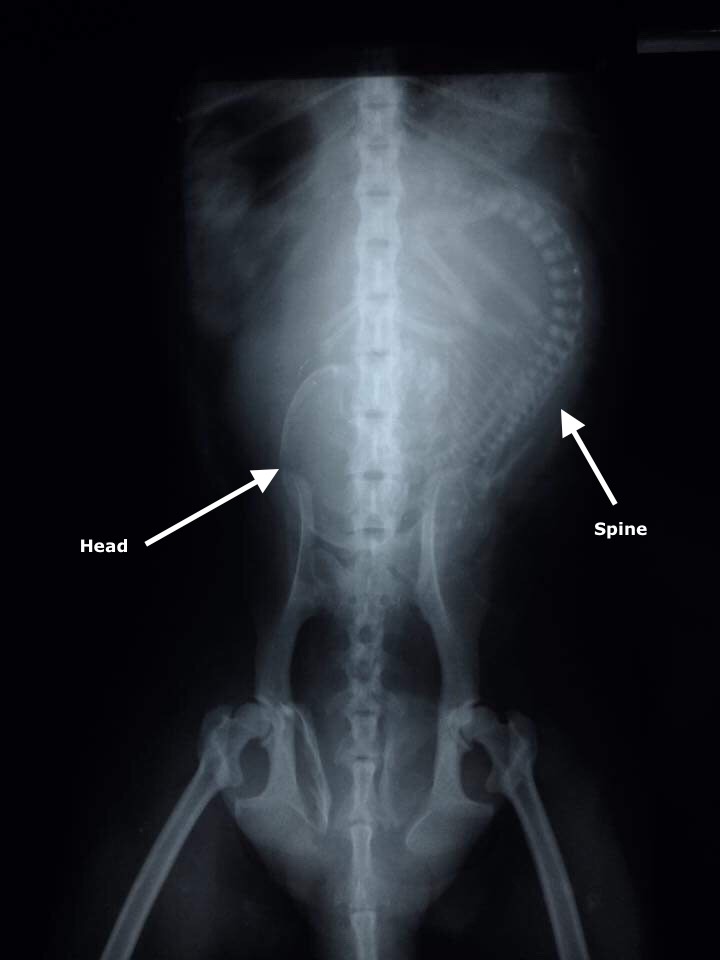

Yesterday we received a report of a badly injured adult female long-tailed macaque (Macaca fascicularis) that was in need of rescue at a Buddhist temple around 1-hour drive from the WFFT Wildlife Rescue Centre. The WFFT Wildlife Rescue Team headed out straight away to help this monkey. Upon arrival to the scene they learned that she had been found lying on the ground since the day before, unable to move and was refusing to take any food or water. After the initial health check it seemed like she had a fractured pelvis so the team took her straight for an x-ray to assess the severity of her injuries. The x-ray indeed revealed that she has a broken pelvis, the team were saddened to find that she was carrying a dead unborn baby which, from x-ray appeared to have a fractured skull. We are unable to ascertain why her baby was dead, it is possible that she had been hit by a car or come into some kind of human-wildlife conflict incident. While the team were getting ready to head back to WFFT they were alerted by another macaque in need, a juvenile female that had been electrocuted then attacked by dogs the previous day. They went to investigate and found that she has sustained terrible burn injures to her legs and has puncture wounds in her skull from the dog attack. Both were transported to the WFFT Wildlife Hospital for urgent treatment.

Upon arrival back to WFFT two teams worked to save the lives of these macaques. The adult female was taken straight to surgery were her unborn baby was removed. The juvenile was sedated so her wounds could be assessed further and tended to. The adult female is currently in a stable condition but has a long way to go if she is to make a full recovery. The juvenile female seems to be recovering well and has a good appetite. We hope they both recover from their terrible ordeals. We will keep you posted on their progress.